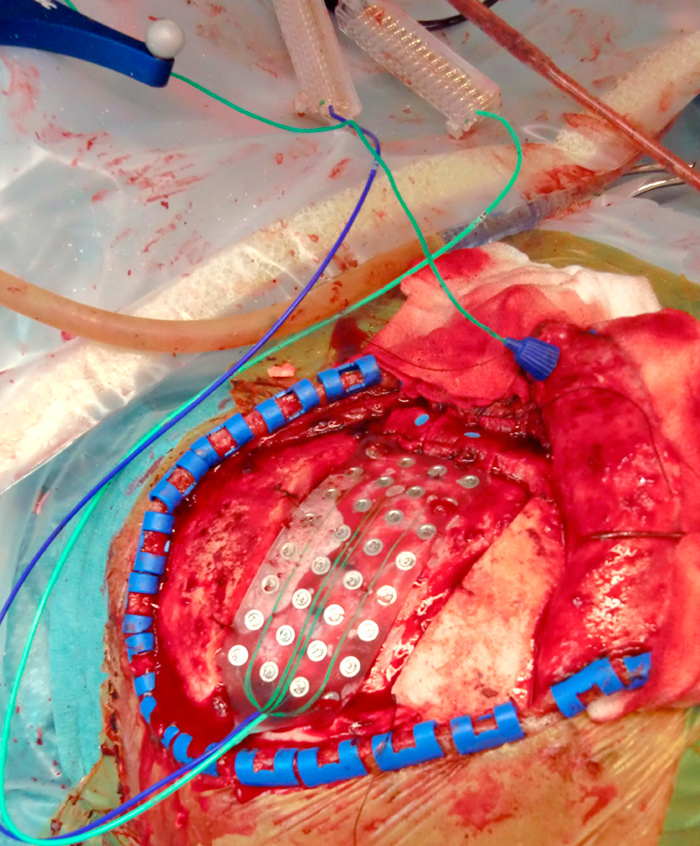

Bildene viser en peroperativ kartlegging av primærmotorisk hjernebark hos pasienten. Kartleggingen skjer med funksjonell MR (fMRi)-bilder og nevronavigasjon, somatosensorisk fremkalt respons (somatosensory evoked potential, SSEP) og elektromyografi (EMG). Målet med inngrepet var å anlegge permanente elektroder over relevante områder av primærmotorisk hjernebark for å lindre kroniske og medikamentelt intraktable smerter.